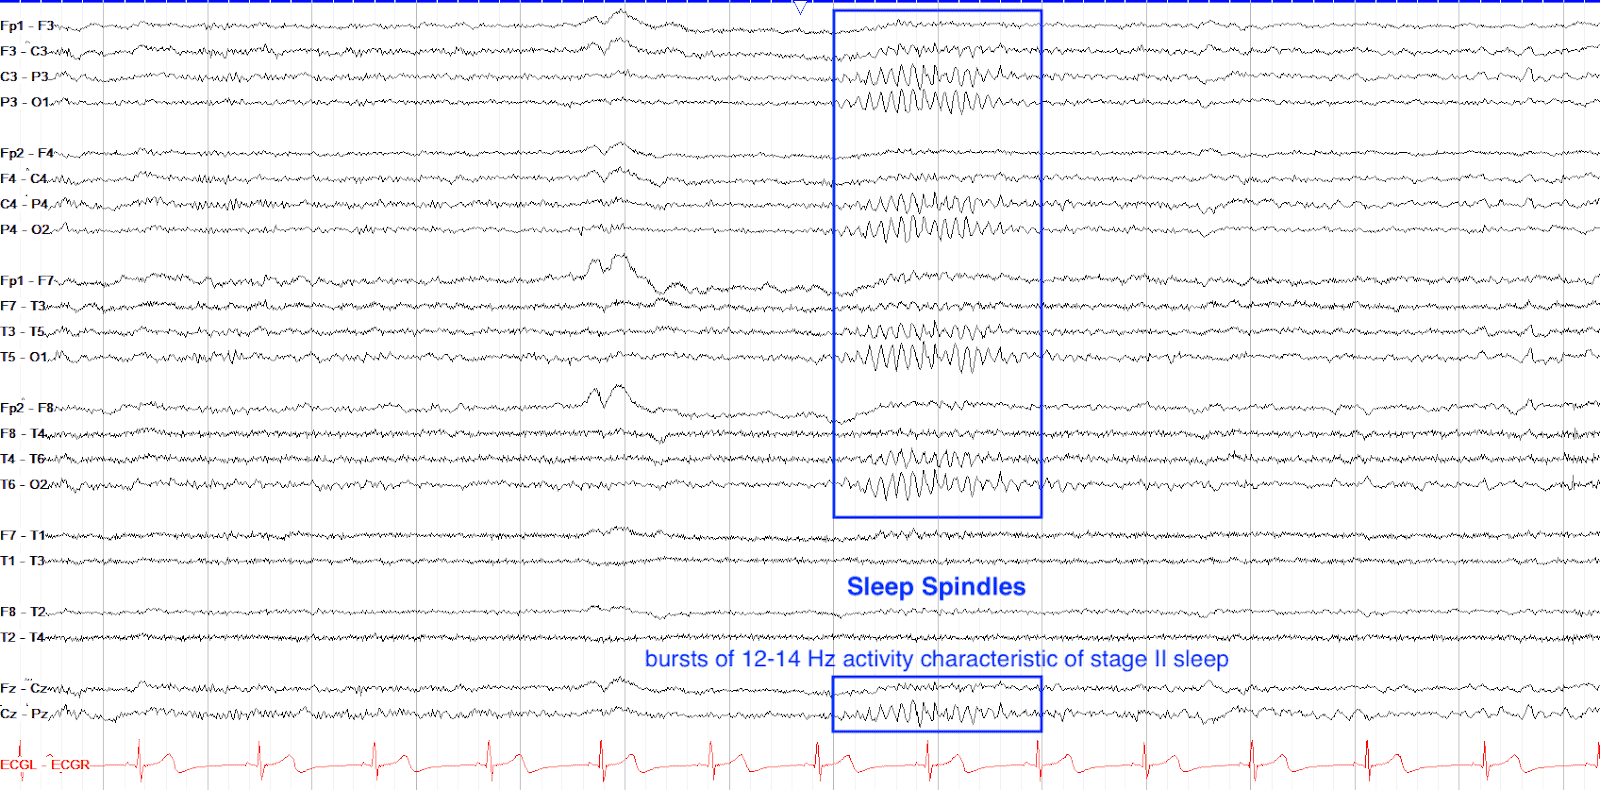

Stage 2 sleep Caris Eeg Recording Shows Sleep Spindles And K-Complexes. What Is Happening — we examine the mechanism of synchronous kc production by creating the first conductance based thalamocortical. this study shows that kcs can be generated across widespread cortical areas. Interestingly, the motor cortex shows. — to this aim, here we characterize in detail sleep spindles in humans using simultaneous recordings of. Caris Eeg Recording Shows Sleep Spindles And K-Complexes. What Is Happening.

sleep spindles Caris Eeg Recording Shows Sleep Spindles And K-Complexes. What Is Happening Interestingly, the motor cortex shows. — to this aim, here we characterize in detail sleep spindles in humans using simultaneous recordings of. this study shows that kcs can be generated across widespread cortical areas. — we examine the mechanism of synchronous kc production by creating the first conductance based thalamocortical. Caris Eeg Recording Shows Sleep Spindles And K-Complexes. What Is Happening.